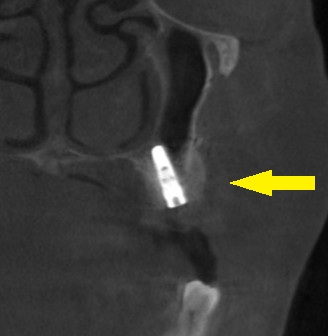

抜歯後3か月でCTを撮ってみたのですが、骨の幅も、高さも足りません(下の写真2段目)。

上方へ少し骨を持ち上げる方法と、頬側には人工骨を補填する方法を併せて行い、インプラント埋入を行なうこととしました。

本日、2本のインプラント埋入と骨造成術を施行しました。

下の写真3段目が手術後のCTです。